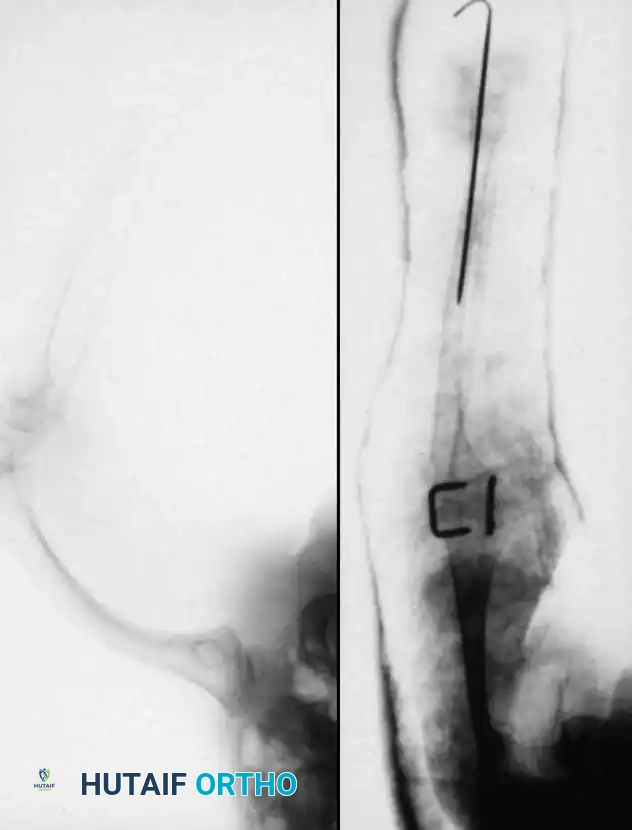

Proximal Tibiofibular Synostosis

For Type 1B and Type 2 tibial hemimelia, centralizing the mechanical axis is critical. The fibula must be brought under the mechanical axis of the femur or the existing proximal tibial anlage.

Technique Overview:

1. A lateral or anterolateral approach is utilized to expose the proximal fibula and the tibial anlage.

2. The proximal fibula is carefully osteotomized or mobilized, taking extreme care to protect the common peroneal nerve, which often has an anomalous course in these patients.

3. The cartilaginous tibial anlage is split or prepared to receive the proximal fibula.

4. The fibula is centralized beneath the tibia/anlage and fixed using smooth Kirschner wires or a small fragment plate, depending on the child's age and bone quality.

5. Bone graft (autograft or allograft) is packed around the synostosis site to promote rapid union.

By fusing the fibula to the tibia, the surgeon prevents the progressive lateral bowing and hypertrophy of the fibula that inevitably occurs if it is left in its native, eccentric position. This synostosis provides a robust, centralized bony column that can later be lengthened or fitted with a prosthesis following a distal Syme amputation.